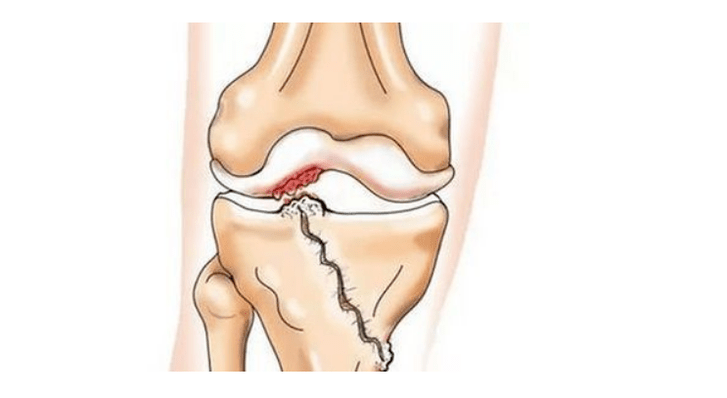

- injuries (fractures, tears of the meniscus and anterior cruciate ligament).Unfortunately, in anyone, regardless of age, these injuries cause excessive stress on the cartilage.A fracture of any part of the bones covered with cartilage is accompanied by the formation of an unevenness - a “step”.In this area, when moving, abrasion occurs and osteoarthritis forms;